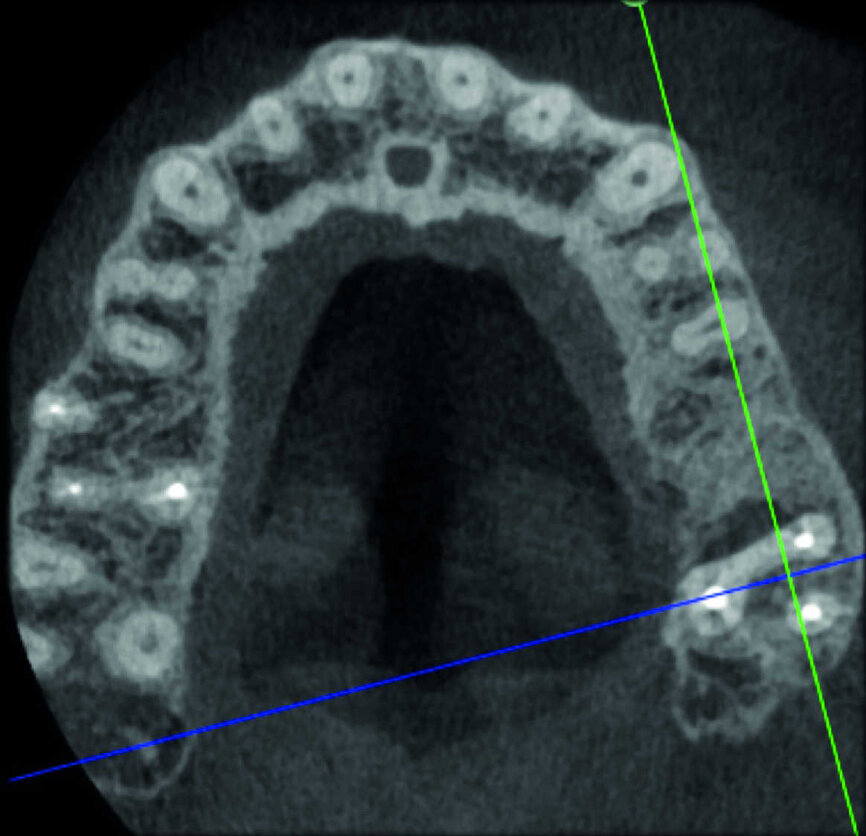

Le cas avec lequel je souhaite commencer mon exposé clinique est un exemple parfait de la difficulté à définir l’origine des symptômes d’un patient, par l’examen d’une simple radiographie intraorale. Non seulement l’examen 2D ne permet pas d’établir avec certitude la présence d’une lésion, mais surtout, il est impossible d’en déterminer la taille, la morphologie et le type. Au contraire, une analyse de l’imagerie 3D offre une image claire de la situation clinique. Chez ce patient, les coupes coronales et sagittales révèlent la présence d’une importante lésion s’étendant de l’apex de la racine mésiale de cette molaire jusqu’à la zone de furcation, tandis que les coupes axiales nous permettent d’analyser précisément l’anatomie endodontique et, en particulier, la forme de la racine mésiale, qui apparaît fusionnée avec la racine palatine. Un panorama complet du cas peut donc guider le processus de décision et orienter le plan de traitement vers une modalité bien précise de traitement (Figs. 1–4).

Indéniablement, l’un des processus pathologiques les plus complexes à traiter est la résorption radiculaire externe invasive, où l’ampleur de la lésion limite les options de traitement. Une évaluation préopératoire de l’emplacement et de l’étendue de la résorption se justifie donc entièrement. Le potentiel de récupération dépend de la planification 3D adéquate de l’intervention, qui ne peut être accomplie qu’après l’examen des clichés CBCT. Il est très important de bien visualiser les coupes de la dent dans les trois plans, et de se concentrer particulièrement sur les coupes axiales, qui s’avèrent stratégiques du point de vue du diagnostic endodontique.

L’évaluation CBCT préopératoire est utile dans les cas nécessitant une approche chirurgicale, non seulement pour confirmer la présence d’une lésion, mais aussi pour planifier l’intervention et, en particulier, identifier le type d’incision chirurgicale à pratiquer, en fonction de la taille et de l’emplacement de la lésion en question (Figs. 23–25). Le cas spécifique présenté dans cet article est caractéristique de cette situation. La radiographie intraorale n’a pas permis de déterminer l’étendue de la lésion, qui touche non seulement la région apicale de la prémolaire, mais aussi un segment édenté en distal. Cette région doit faire l’objet d’un traitement régénérateur, afin de garantir la cicatrisation appropriée de la zone, suivi par la mise en place d’une membrane. Une approche totalement différente de celle requise pour la chirurgie endodontique doit être utilisée pour protéger le lambeau. Les différentes étapes de l’intervention sont illustrées dans les images peropératoires (Figs. 26–28). L’examen CBCT réalisé 12 mois plus tard, confirme la cicatrisation complète de la lésion apicale et la parfaite intégration de la greffe (Figs. 29–31).